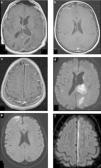

En los últimos años, se ha destacado la importancia de utilizar esta secuencia con pulsos de saturación grasa y luego de administrar el medio de contraste: mientras la primera aumenta el contraste entre la sustancia gris y blanca, con una mejora consiguiente de la resolución; la poscontraste tiene una mayor sensibilidad en la detección de alteraciones meníngeas, tanto de colecciones líquidas (sobre todo empiemas subdurales) como del compromiso leptomeníngeo observado en las meningitis de distinta etiología8–10 (fig. 1).

Paciente con meningitis tuberculosa confirmada. Se muestra la utilidad y los hallazgos de la secuencia FLAIR luego de administrar el contraste. (a, b y c) En los cortes axiales se identifica el intenso realce y la ocupación de la cisterna de Silvio del lado derecho por el depósito de material granulomatoso (característico de esta patología). (d, e y f) Mismo paciente: en los cortes sagital y axial de la secuencia SE ponderada en T1 con contraste se observan los hallazgos ya identificados claramente en la secuencia anterior.

Algunos autores sugieren que la sensibilidad de las secuencias FLAIR posgadolinio y las ponderadas en T1 es idéntica en el diagnóstico de la patología infecciosa leptomeníngea, pero que la FLAIR tiene mayor especificidad10. Incluso, otras comunicaciones, como la de Splendiani et al.11, demuestran la utilidad de la RM con secuencias FLAIR poscontraste en el diagnóstico precoz de casos con meningitis infecciosa. No obstante, a pesar de estos estudios y de que nuestra experiencia sea muy similar en un número significativo de pacientes, es necesario destacar que las secuencias convencionales ponderadas en T1 con contraste no son sustituibles en esta población.